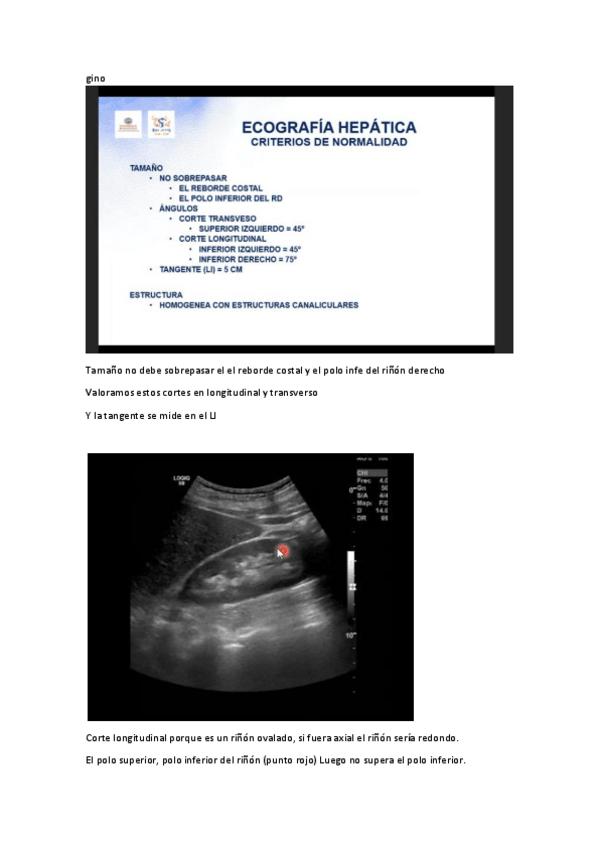

Rx Abdominal

He publicado nuevos apuntes de 3º radiología y medicina nuclear: Rx Abdominal

Estudio-radiologico-higado-5.pdf

Estudio-radiologico-higado-6.pdf

Estudio-radiologico-higado-2.pdf

Estudio-radiologico-higado-4.pdf